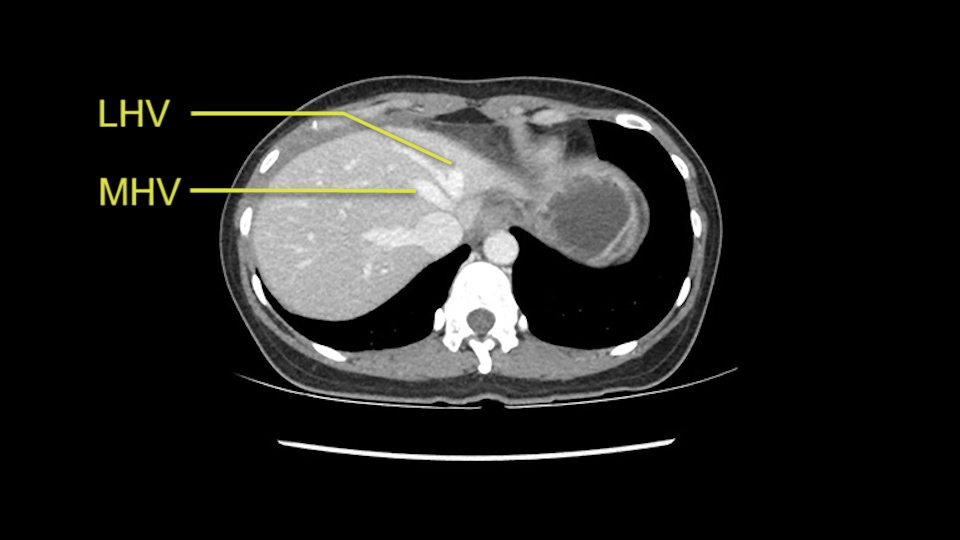

The transection line will be a little more obvious. There’s a little patch of focal fat here in Segment 4b but we’ll describe the transection line probably through the mid portion of Segments 4a and b up to the top. Up at the top, the left hepatic vein can be taken. There’s a Segment 3 vein or the so-called falciform vein it’ll be rudimentary so I think we’ll be able to get around the left hepatic vein and leave the middle [hepatic] vein intact because it’s free of tumor.

The other option of course is to do an anatomical left hepatectomy. In that case, I will start mobilizing of course the left lobe and try to find the ligamentum venosum, take it down and go around the left hepatic vein. I think, importantly in these cases and in this case, as you can see in the venous phase, that’s clearly a moment to stop. Because the left hepatic vein is pretty close to the middle hepatic vein as sometimes it is so you may need to dissect a little bit the parenchyma on top of the left hepatic vein to be able to go around the left hepatic vein safely.